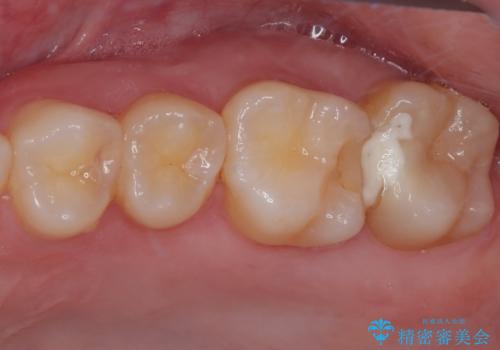

- 奥歯の歯肉から定期的に膿が出てくるとのことで来院された患者様です。

レントゲン写真などの診察を行った結果、根管治療が必要であったため、現在のクラウンを除去し、根管治療を行うこととしました。

根管治療後は症状を確認し、速やかにオールセラミッククラウンにて補綴治療を行うこととしました。